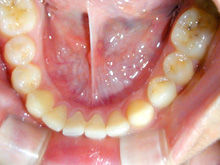

下顎前歯の叢生の改善のために部分矯正を希望されました。下顎の前歯群には中等度の叢生がみられます。

神経系の慢性疾患のためお薬の副作用の影響で歯肉の腫脹が目立っています。

下顎前歯の叢生の改善するためには上下顎前歯の接触が緊密なために上顎の前歯の矯正治療が必要となります。

臼歯関係、犬歯関係ともに1対2歯でよく咬んでいますので

咬み合わせの関係を壊すことなく上下顎の前歯の叢生を部分矯正で改善をめざします。

側貌から口元には緊張がなく突出を認めなかったので非抜歯で矯正治療できると患者様にはお伝えしました。

薬物の副作用の影響の歯肉の腫れは叢生の改善によりブラッシングが容易になると改善されることを期待します。

上下顎の前歯を前方へ移動させ、その状態により前歯のストリッピングを行うなどを計画します。